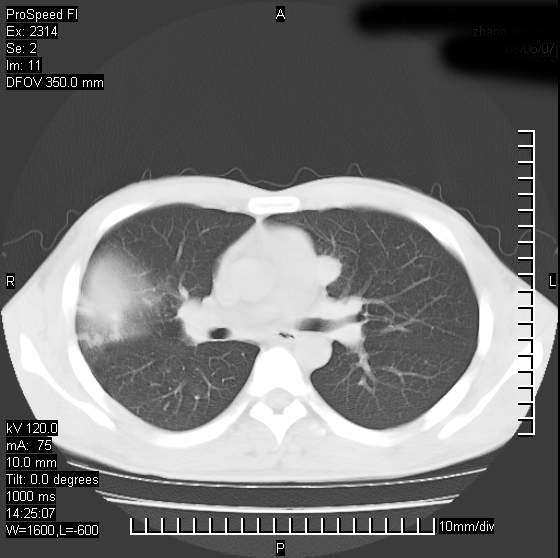

男性,再生障碍性贫血,入院前发热10天,最高40c,右侧胸痛,外院ct示右上,中肺边缘模糊的球性影(就是我现在图中标示的范围),考虑炎症,在我院使用头孢呋辛,洛美沙星10天,高烧消退,自感下午稍有发热,但今天ct示右上,中肺病灶明显扩大,还是考虑炎症,看其中的球型影是否霉菌感染??,是否能排除结核?

右肺中叶外侧段病变,上缘界限不清,下缘锐利,以段性发病为主,内见巨大空洞及空洞内容物,结合病史首先考虑:化脓性肺炎。不除外霉菌感染!

片状高密度影内见空洞影,内可见球形软组织密度影,并有新月征,考虑霉菌感染.

支持右肺上叶、中叶外侧段节段性肺炎伴脓肿形成。